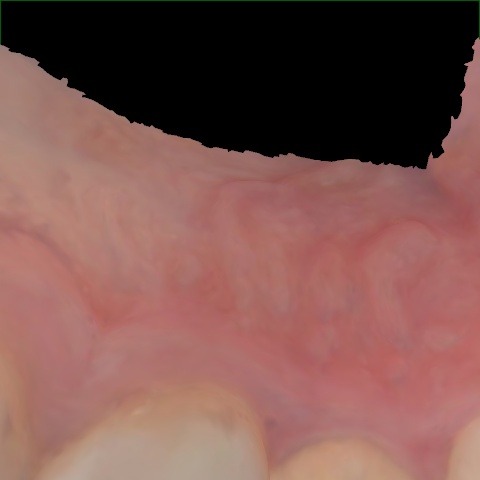

Annotated as "Good"